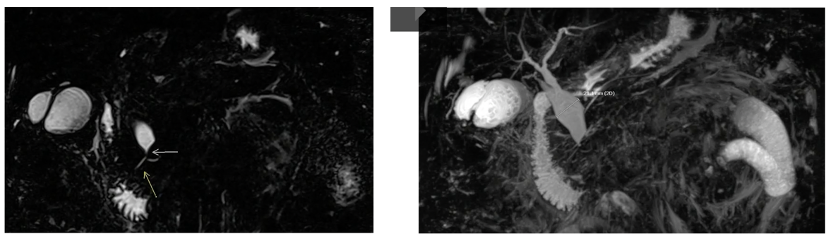

Caroli’s syndrome